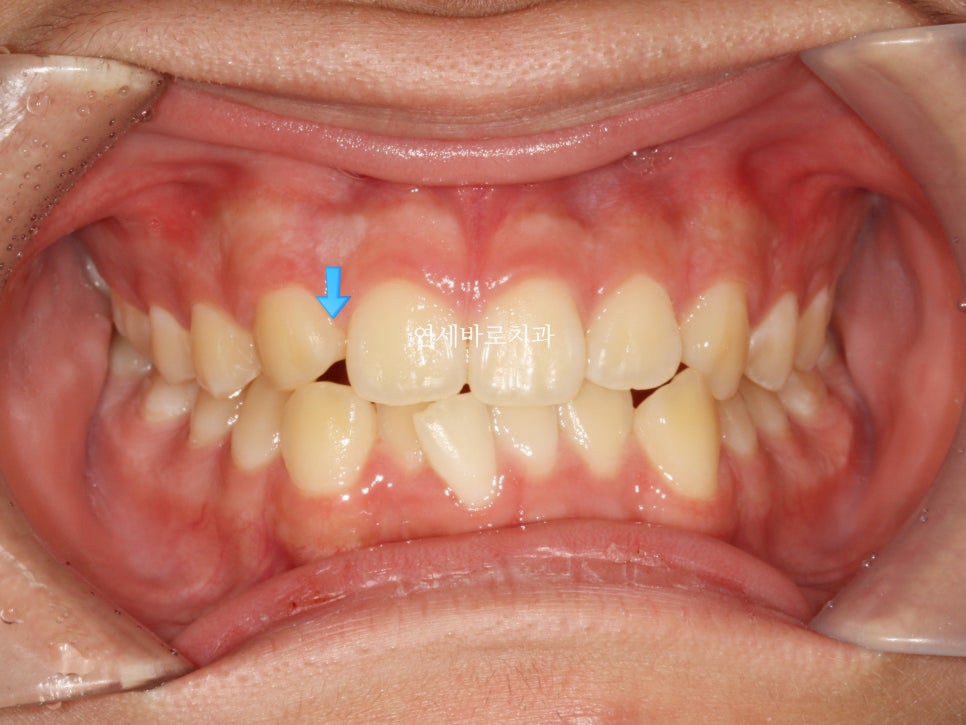

비대칭이 많이 개선된 것으로 보이며,

화살표 부분이 원래 치아가 하나 더 있어야 하는 곳인데 없는 부분을 나타내는 곳입니다

그리고 아래쪽 앞니는 아이의 골격과 치아관계를 고려하여 일부러 공간확보를 하지 않았습니다.

발치를 하기로 했거든요